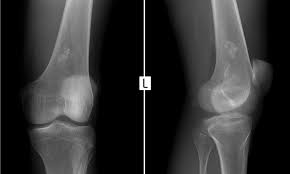

육종암 의심 증상은 해당 부위 통증이라고 한다. 다리, 골반 등이 아프다고 한다. 가벼운 운동이나 스트레칭을 하다가 뼈에 금이 가거나 골절이 생겨 엑스레이 사진을 찍어 발견하는 경우도 있다고 한다.